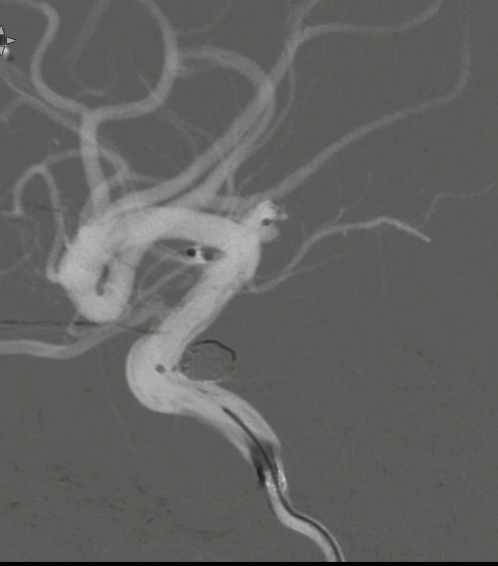

工作位侧位造影(图片)

工作位侧位造影(视频)

6F Envoy DA在泥鳅导丝辅助下超选至右侧颈内动脉海绵窦段后膝。

继续填入Target 1.5/2弹簧圈成篮,后完全释放支架,其近端位于颈内动脉分叉处,远端位于A1远端。

术后正侧位造影:Raymond Ⅲ级